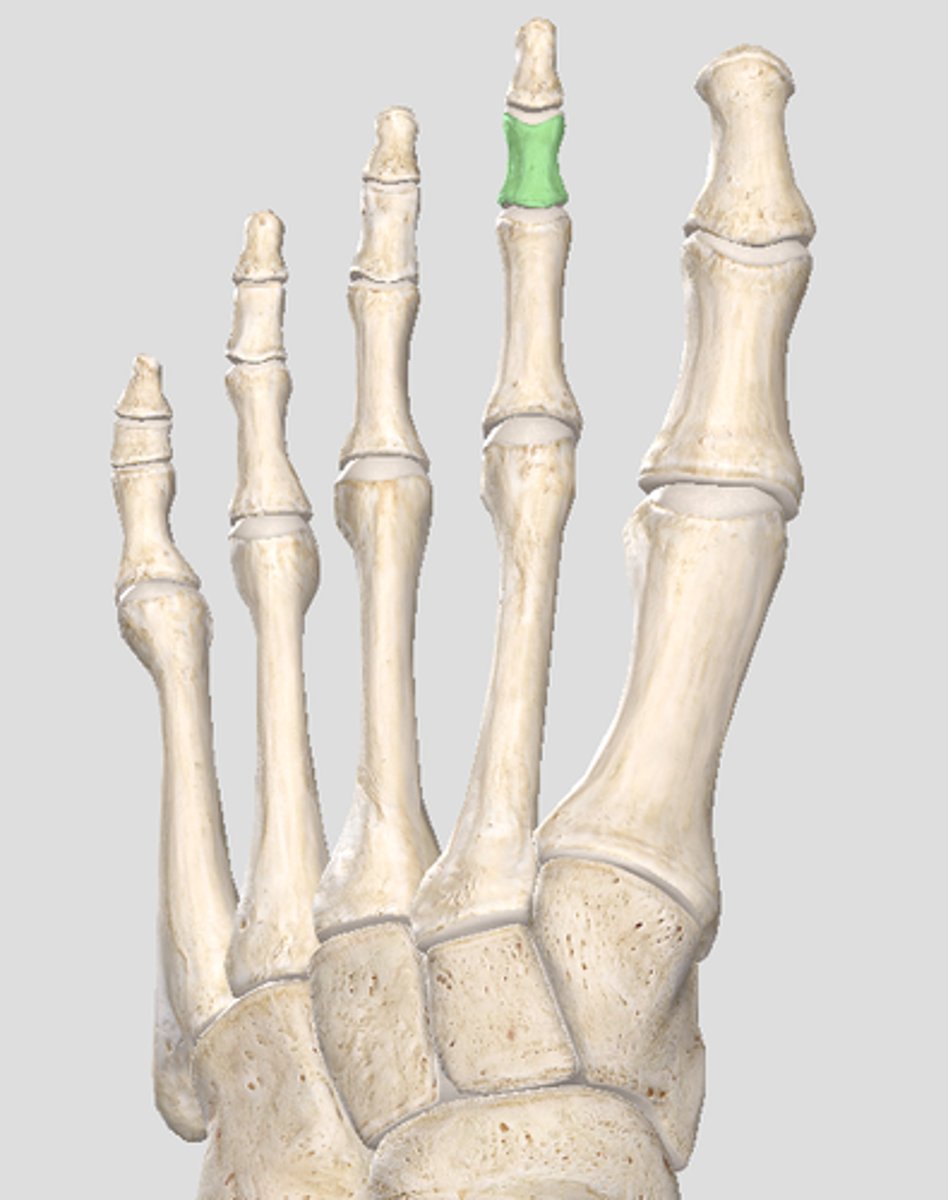

Middle phalanx of digit 2

Distal phalanx of digit 2